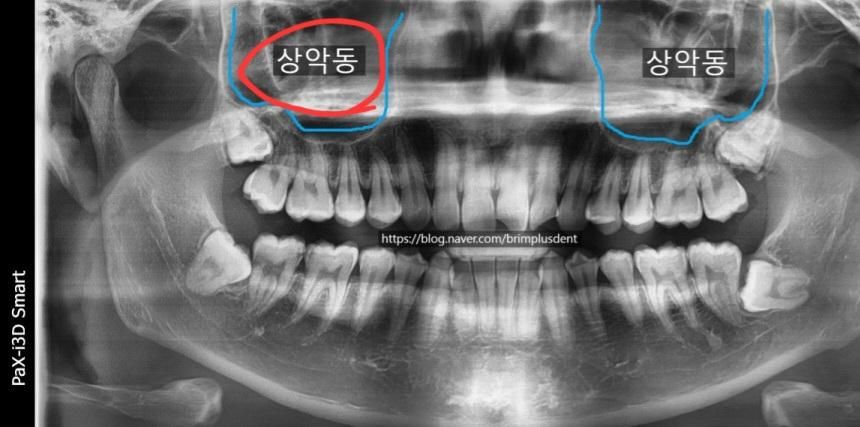

부비동?상악동?에 혹이보인다는데요

스케일링 때문에 치과가서 엑스레이찍었는데

부비동?상악동?에 사진빨간동그라미크기의 혹?같은게보이더라구요.

보통은 이상없는데 찝찝하면 큰병원가서검사하라던데요ㅠㅠ뭔지알려주세요